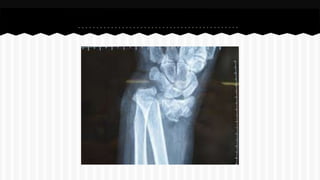

RESPONDA O NOME DO OSSO EM QUE

SE ENCONTRA A (S) FRATURA (A).